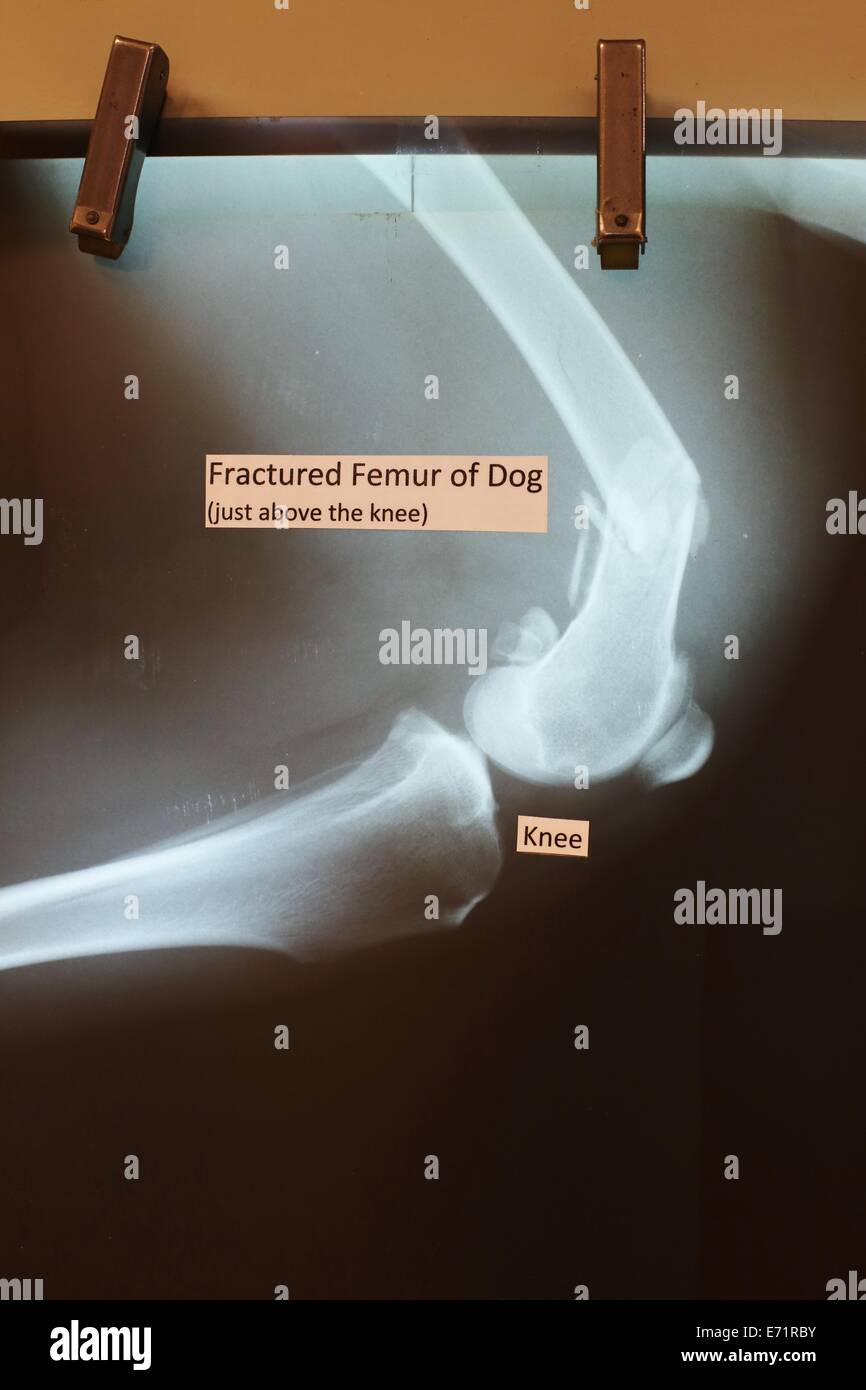

An x ray of a dog's broken femur on display at the Minnesota State Fair Can A Dog's Broken Femur Heal On Its Own After surgery and discharge from the hospital, the dog must be restricted from activity to allow the fracture to heal properly. In order to better understand the process of healing, it helps to gain a closer insight into how bones are structured and how different types of fractures impact them. A femur fracture can have serious consequences for your dog’s. Can A Dog's Broken Femur Heal On Its Own.